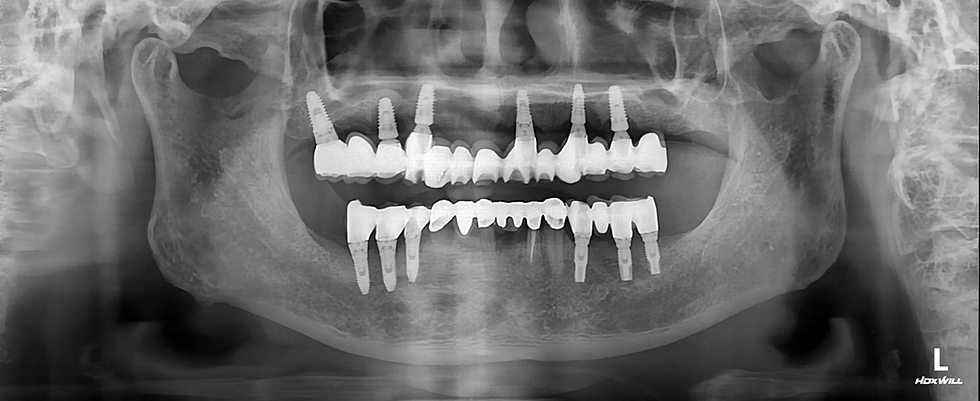

Post operative panoramic view

Intraoral and panoramic views after delivery of final prosthesis